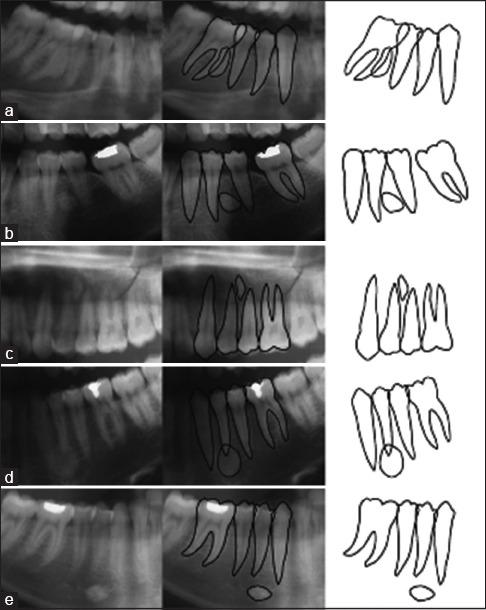

IO was detected in 31 (7.5%) patients and 22 (68.8%) lesions had exact border while their shape was mostly irregular. About 17 (53.1%) lesions were apical, and 13 (40.6%) lesions had no relation to the teeth. The most involved teeth were the second premolar (28.1%) and first molar (25%). Moreover, CO was detected in 32 (7.8%) patients. 17 (53.1%) lesions had an ill-defined border, and their shape was mostly irregular (65.6%) with ill-defined border. Around 18 (56.3%) lesions were apical, and 11 (34.4) lesions were apical and interradicular. The most involved teeth were the second premolar (59.4%) and the first molar (21.9%).

在31例(7.5%)患者中检测到IO,22个(68.8%)病灶边界清晰,其形状大多不规则。约17个(53.1%)病灶位于根尖部,13个(40.6%)病灶与牙齿无关。受累最多的牙齿是第二前磨牙(28.1%)和第一磨牙(25%)。此外,在32例(7.8%)患者中检测到CO。17个(53.1%)病灶边界不清,其形状大多不规则(65.6%)且边界不清。约18个(56.3%)病灶位于根尖部,11个(34.4%)病灶位于根尖部和根间。受累最多的牙齿是第二前磨牙(59.4%)和第一磨牙(21.9%)。